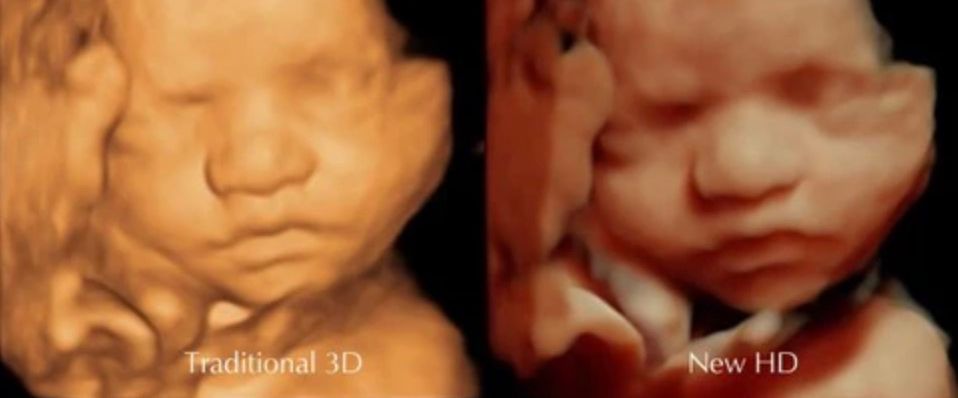

2d, 3d,4d & HD live

Enjoy a private, affordable ultrasound from the comfort of your home, perfect for moms between 7–41 weeks. Share the moment with loved ones by connecting directly to your TV for real-time viewing in 2D, 3D, or 4D. Ideal for baby showers or gender reveal parties!